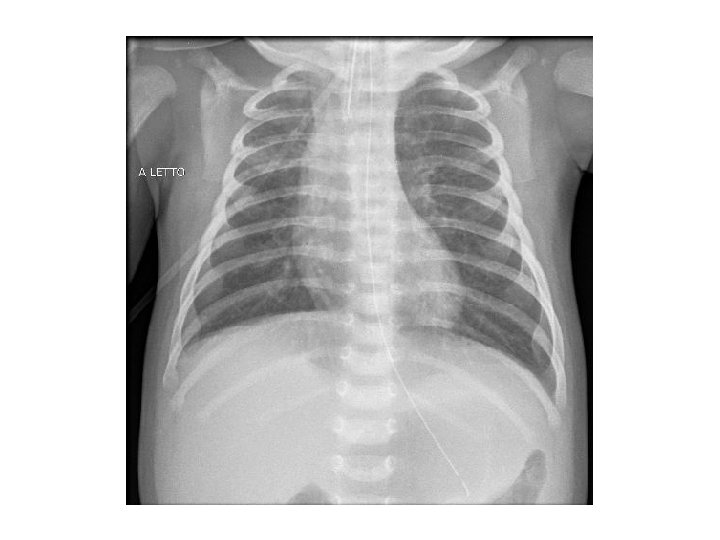

Ricovero in TIN 05/02 SIMV 06/02 estubata IMV con Ram cannule 07/02 respiro spontaneo in aa PCR per RSV su TN POSITIVA PCR per Bordetella pertussis su TF NEGATIVA PCR virus influenzali, adenovirus, rhinovirus NEGATIVA Colturale su BAL NEGATIVO Esami ematici nei limiti della norma, PCR negativizzata

07/02